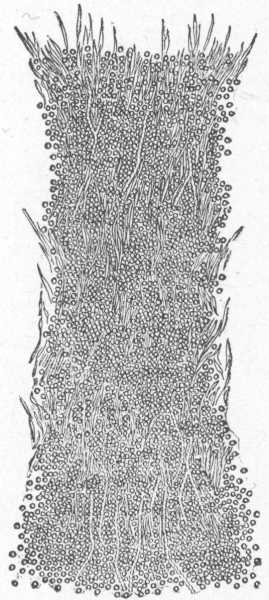

Fig. 6.

A normal sweat-gland, highly magnified. (After Neumann.)

a, Sweat-coil: b, sweat-duct; c, lumen of duct; d, connective-tissue capsule; e and f, arterial trunk and capillaries.